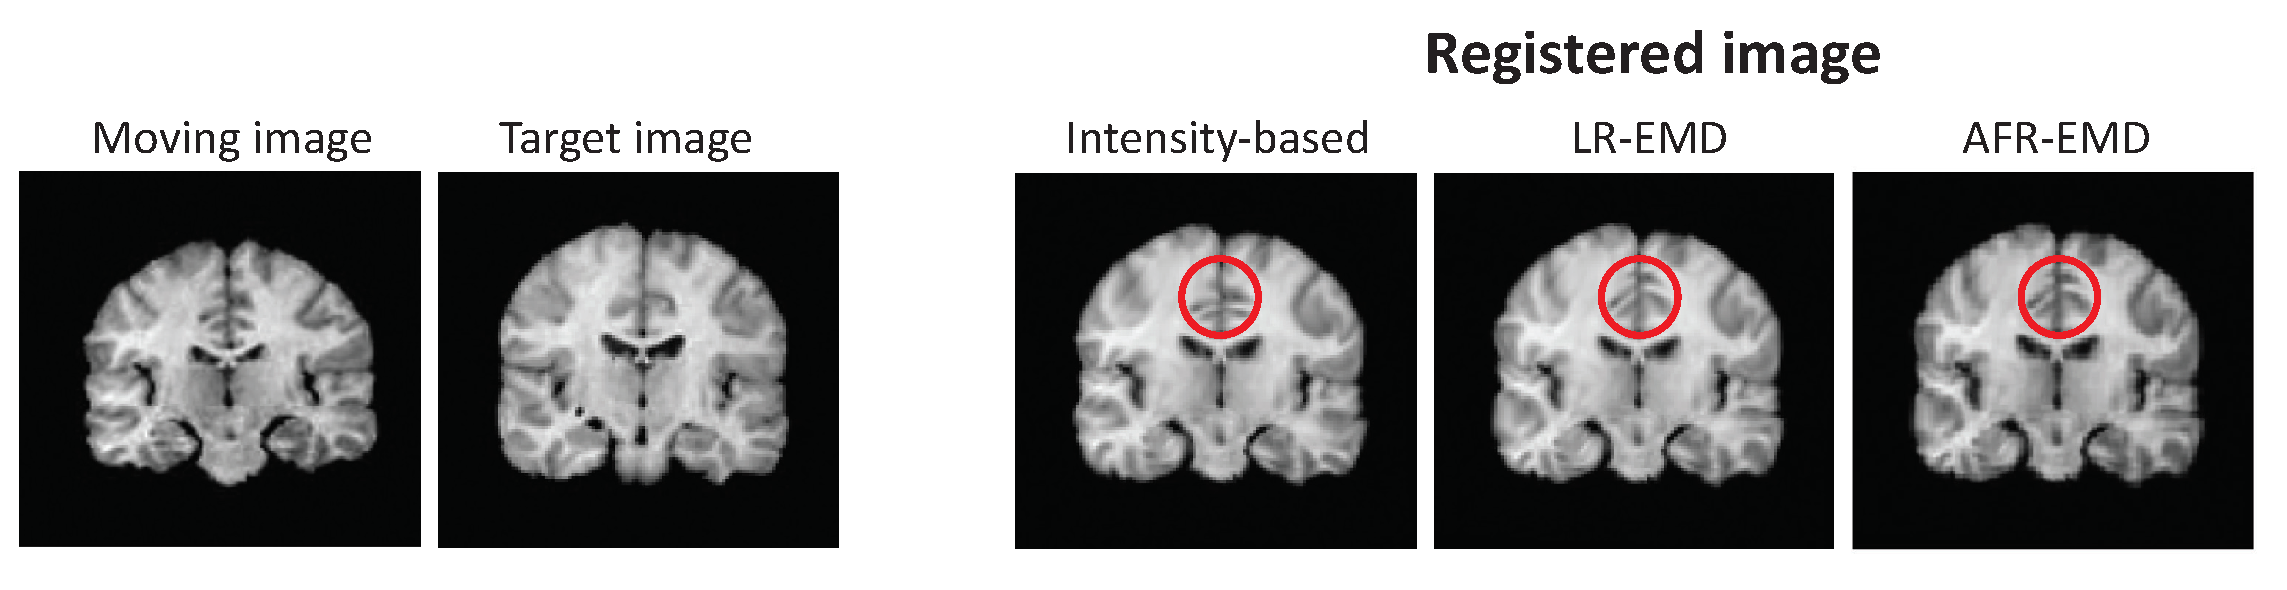

3.1. Evaluation of the Proposed Algorithms on the MRIs from the BrainWeb Dataset

3.2. Evaluation of the Proposed Algorithms on the MRIs from the IBSR Dataset